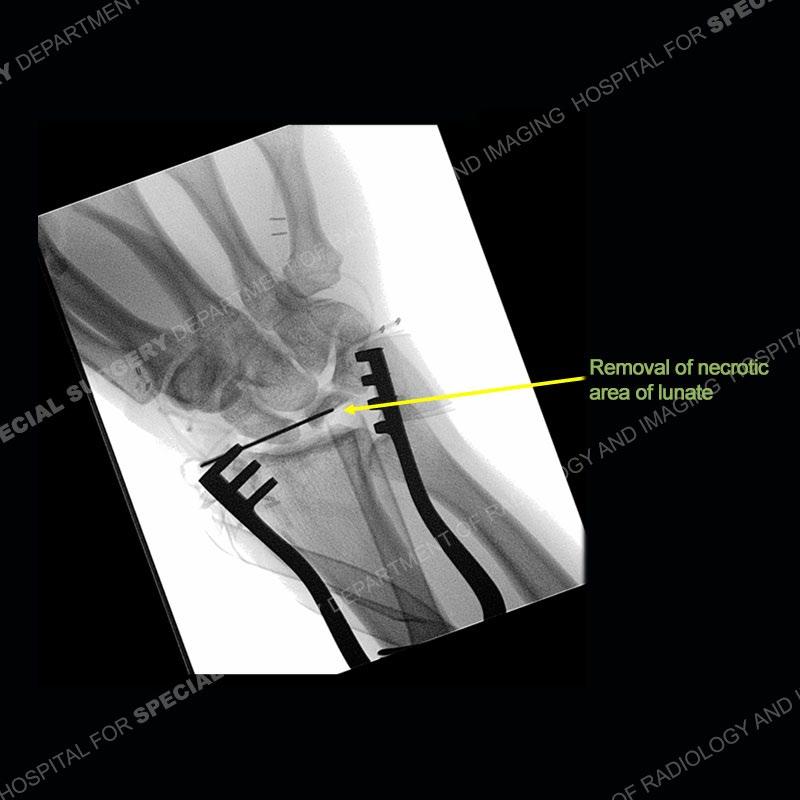

Both cases demonstrate similar findings to slightly less and more conspicuous degrees. The radiographs show sclerosis and fragmentation/collapse of the lunate. The CT images for case one just further clarify the architecture of the lunate. The MRI images show a slightly greater degree of variability but with overall persistent areas of low signal of the lunate on all pulse sequences and with a loss of the geometry of the lunate indicating collapse and fragmentation.

Diagnosis: Kienbock’s Disease

A well recognized but still poorly understood entity with necrosis and collapse representing the end stage of the pathology. The reasons for the necrosis are likely multifactorial and relate to the anatomy of the wrist inclusive of ulnar variance and the anatomy of the vasculature to the lunate. Other inflammatory, biological processes and overuse/trauma also likely play a role in the development of the necrosis. The disease manifests by sclerosis of the lunate followed by collapse and fragmentation. This is then followed by abnormal orientation of the scaphoid in a palmar flexed position and then adjacent arthritis. These latter processes were not the focus of this case presentation. The MRI will show areas of low signal on all pulse sequences indicating the areas of devitalized bone. The foci of slightly increased signal are in keeping with areas of maintained perfusion and highlight the variable architecture and findings of Kienbock’s. The fragmentation and collapse of the bone are seen well on both CT and MRI.

Diagnosis Continued:

The treatment as the underlying cause of Kienbock’s remains somewhat elusive. Prior to collapse, osteotomies to decrease load or shearing forces to the lunate may be helpful. Once collapse and arthritis have been engendered, fusion and carpectomy have been performed. Now, the role for vascularized bone grafting is being investigated with long term results still being somewhat lacking. Given the young age of the second patient and lack of adjacent, advanced cartilage wear, a vascularized bone graft was performed. The area of necrotic bone was excised, a vascularized bone graft from the distal femur was harvested, and then using microsurgical technique it was grafted to the lunate. A temporary fixation was performed and once the graft was incorporated, the fixation hardware was removed. Although still early in the postoperative period, the patient is doing well.